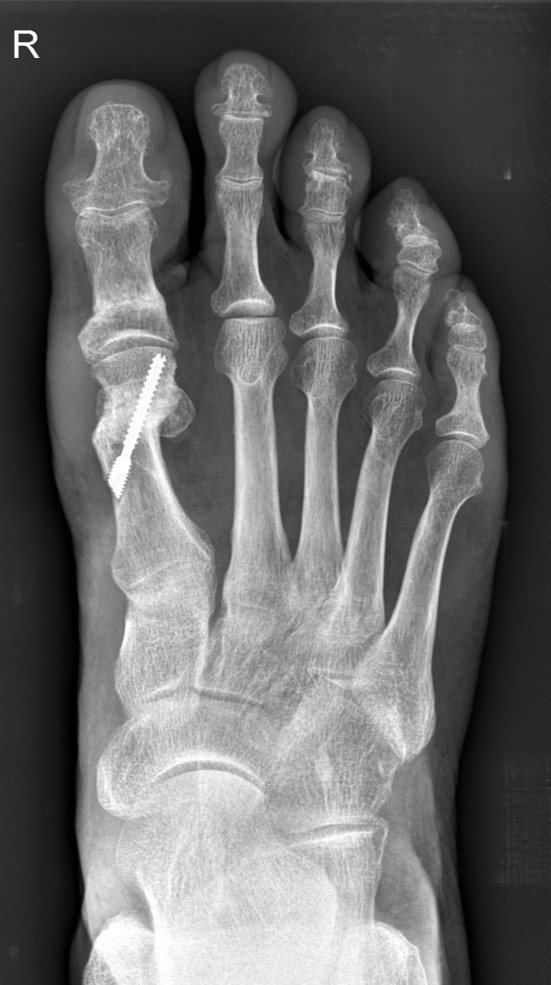

• 6 Wochen postoperativ Röntgenkontrolle in 2 Ebenen (dorsoplantar, lateral). Weitere Röntgenkontrolle in 2 Ebenen 6 Wochen später.

• Hallux valgus-interphalangeus-Rezidiv: Ein solches tritt auf, wenn bei der Osteotomie zuviel Knochen lateral verbleibt und die Spannung der lateralen Knochenbrücken ausreicht, den Osteotomiespalt wieder aufzudehnen. Eine zweite Ursache kann darauf beruhen, daß die Suturestrip Anlage nicht durchgeführt worden ist bzw. eine unzureichende Verbandsanlage postoperativ vorgenommen worden ist. Nach erfolgter knöcherner Konsolidierung ist eine neuerliche Korrektur mittels Reosteotomie möglich. In jedem Fall muß eine genaue radiologische Analyse zur optimalen Planung der Korrektur und die Verwendung einer Schraube empfohlen werden (siehe auch Minimalinvasive Chevron- und Akin-Osteotomie).